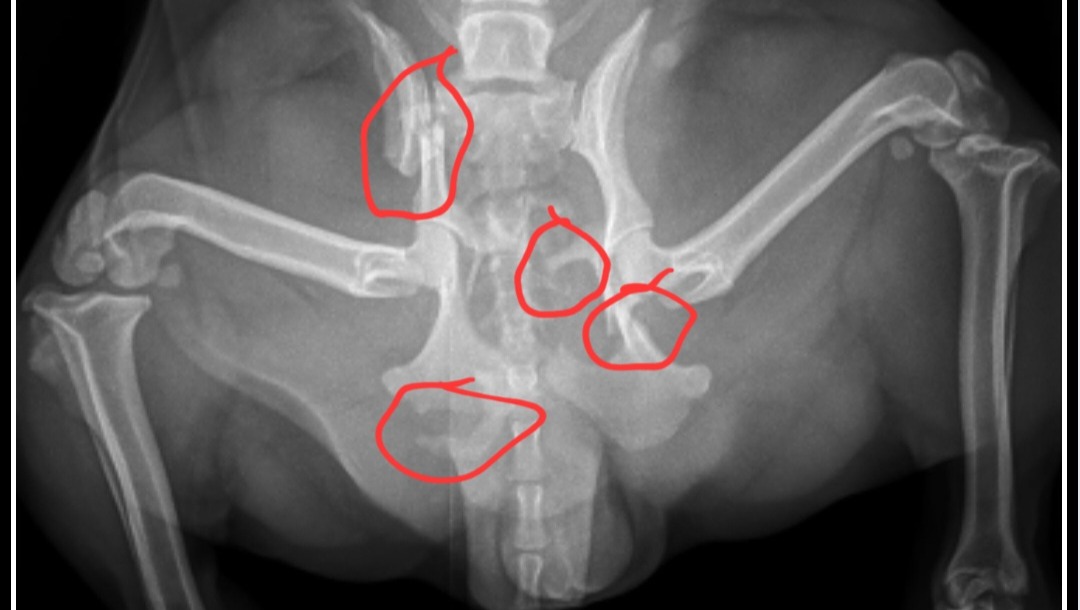

Hi, my name is Justin, and I’m fundraising for my sweet dog, Gidget. She’s only 1 year and 8 months old, full of life and love, but recently she was hit by a car and suffered multiple pelvic fractures—her pelvis is broken in four different places. She’s an incredibly strong girl, but she can’t heal properly without surgery.

Right now, Gidget can’t stand, walk, or even go to the bathroom on her own. This type of injury will not heal by itself—surgery is the only way she can recover. Without it, I’ll be forced to make the heartbreaking decision to put her down, something I don’t want to do when she’s still so young and has so much life ahead of her.